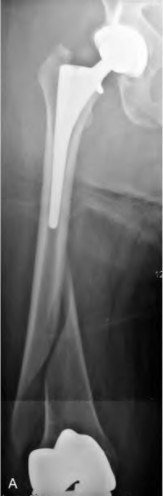

An 82-year-old woman falls and sustains the fracture shown in figure A. She denies any history of dislocation or prodromal pain prior to her fall. What is the most appropriate treatment?

The radiograph demonstrates a periprosthetic femur fracture extending to the tip of the stem. The long spiral fracture is consistent with a loose implant. The bone stock is sufficient. Therefore, this fracture pattern would classify as a B2 using the Vancouver classification system. The Vancouver classification for periprosthetic femoral fractures is simple yet incorporates all the pertinent factors such a location, stem fixation, and bone stock. Type A is a trochanteric fracture- lesser or greater. These can be treated non-operatively usually and ORIF if symptomatic. Type B fractures are around or just below the stem and are subdivided into three types. Type B1 is a fracture with a well fixed stem.

The treatment is cable plating or allograft struts or a combination of the two. Type B2 is a fracture with a loose stem with good bone stock. The treatment is a cementless porous coated long stem atleast two diameter length past the

fracture site. Type B3 is a fracture with a loose stem and comminution. For younger patients, use cementless porous coated long stems with allograft struts. For older patients, consider a tumor prosthesis. Cement fixation is sometimes necessary Type C is a fracture well below the stem tip. These can be treated independently of the prosthesis.

Springer et al showed optimal outcomes with revision involving long extensively-coated femoral stems for Vancouver B fractures.

Masri et al review the classification and treatment of periprosthetic femur fractures.

A 72-year-old male presents 2 years status post fixation of an impending pathologic right femur fracture due to metastatic renal cell carcinoma. He is minimally ambulatory due to pain. Despite radiation therapy, there has been progression of the lesion with extensive cortical bone loss, which is shown in Figure A. A proximal femoral replacement arthroplasty is performed without complications, and is demonstrated in Figure B. Which of the following is true regarding this patients post-operative course?

Deep prosthetic infection is the most common complication after hip arthroplasty performed for salvage of failed internal fixation after pathologic proximal femoral fracture secondary to malignancy.

Jacofsky et al reviewed the complications in 42 patients with a mean age of 63 who were treated with hip arthroplasty for salvage of failed treatment of a pathologic proximal femoral fracture. Multiple different constructs were used.

The most common complication was deep prosthetic infection, which occurred in nearly 10% of the patients studied. All infections occured in patients whom had previously received radiation. The mean Harris Hip score improved from 42 to 83 points post-operatively, and 41 of the 42 patients were ambulatory at follow-up. Implant survivorship free of revision for any reason at 5 years was 90%, and free of revision for aseptic failure or radiographic failure was 97%.

Figure A shows a lytic lesion of the proximal femur with an intramedullary implant. Figure B shows a proximal femoral replacement.